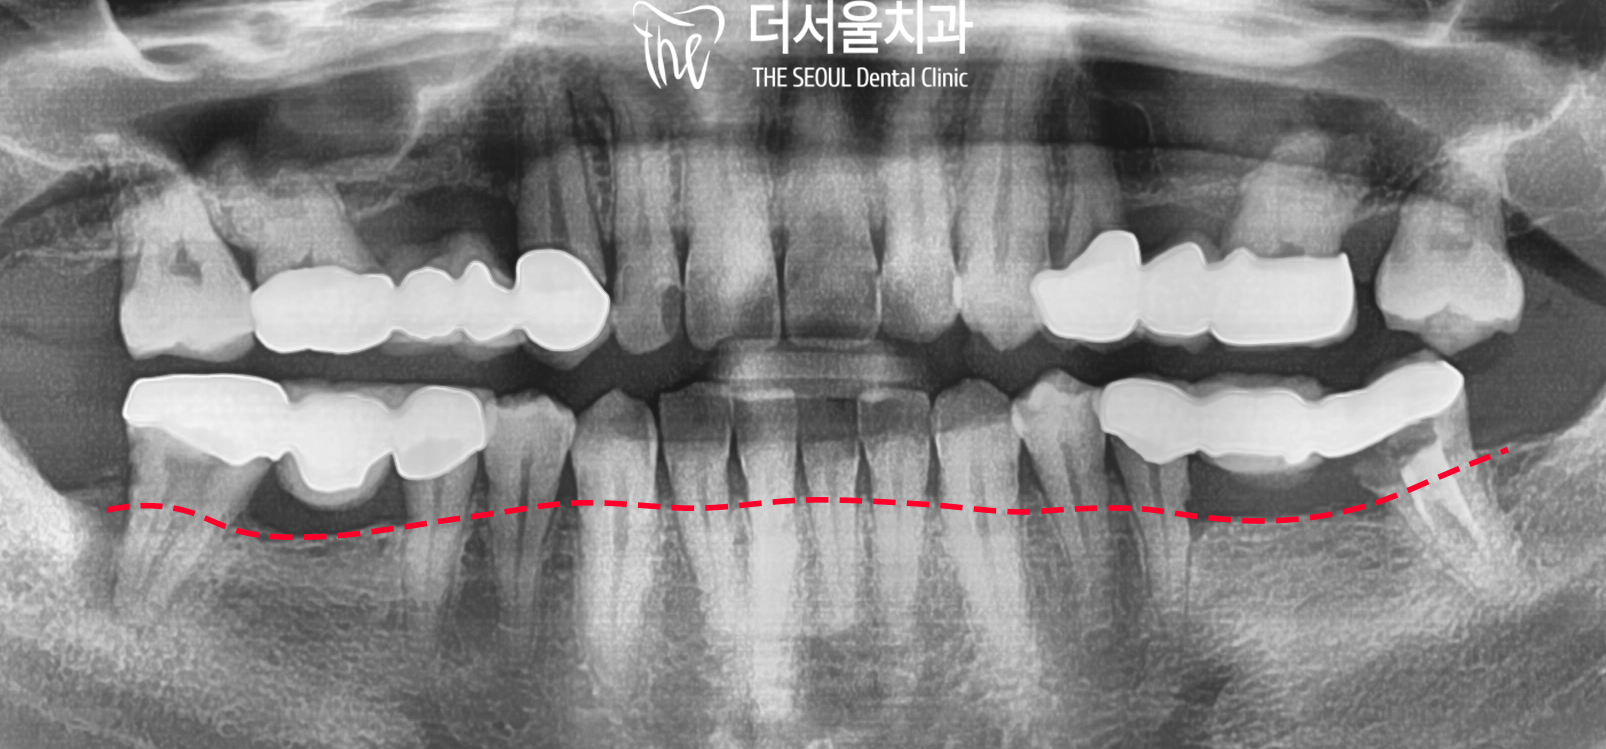

꼼꼼한 검진을 위해

x-ray를 찍어봤습니다.

표시해 둔 곳이 치조골이

내려앉아 치아뿌리를 거의 잡아주지 못하고 있어

아래쪽 어금니가 흔들리고 있습니다.

사실상 양쪽 어금니가 둘 다 문제가 있어

구치부 기능을 못 하고 있는 것인데요.